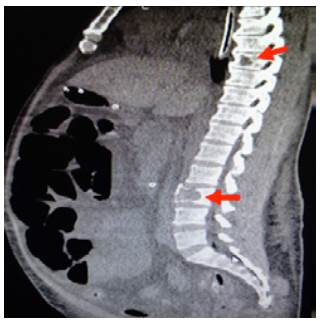

On admission, myopathy studies were initiated (Table 1) and muscle enzymes, electromyography and muscle biopsy were requested, which excluded inflammatory myopathy. The autoimmune profile and HIV were negative. Adult Pompe disease was considered, but acid maltase was normal and syringomyelia was ruled out using contrast-enhanced cervical and brain MRI (Figure 3). Considering the lytic lesions observed in chest tomography, neoplasms (myopathy as a paraneoplastic phenomenon) were looked for as there was no compromise of the pulmonary parenchyma, only bibasal subsegmental atelectasis. No masses or organomegaly were observed in abdomen images (Figure 4).

Sagittal CT scan of contralateral abdomen: distended loops and lytic lesions in T8 and L3 (arrows).

Figure 4: Sagittal CT scan of contralateral abdomen: distended loops and lytic lesions in T8 and L3 (arrows).

Source: Own elaboration based on the data obtained in the study